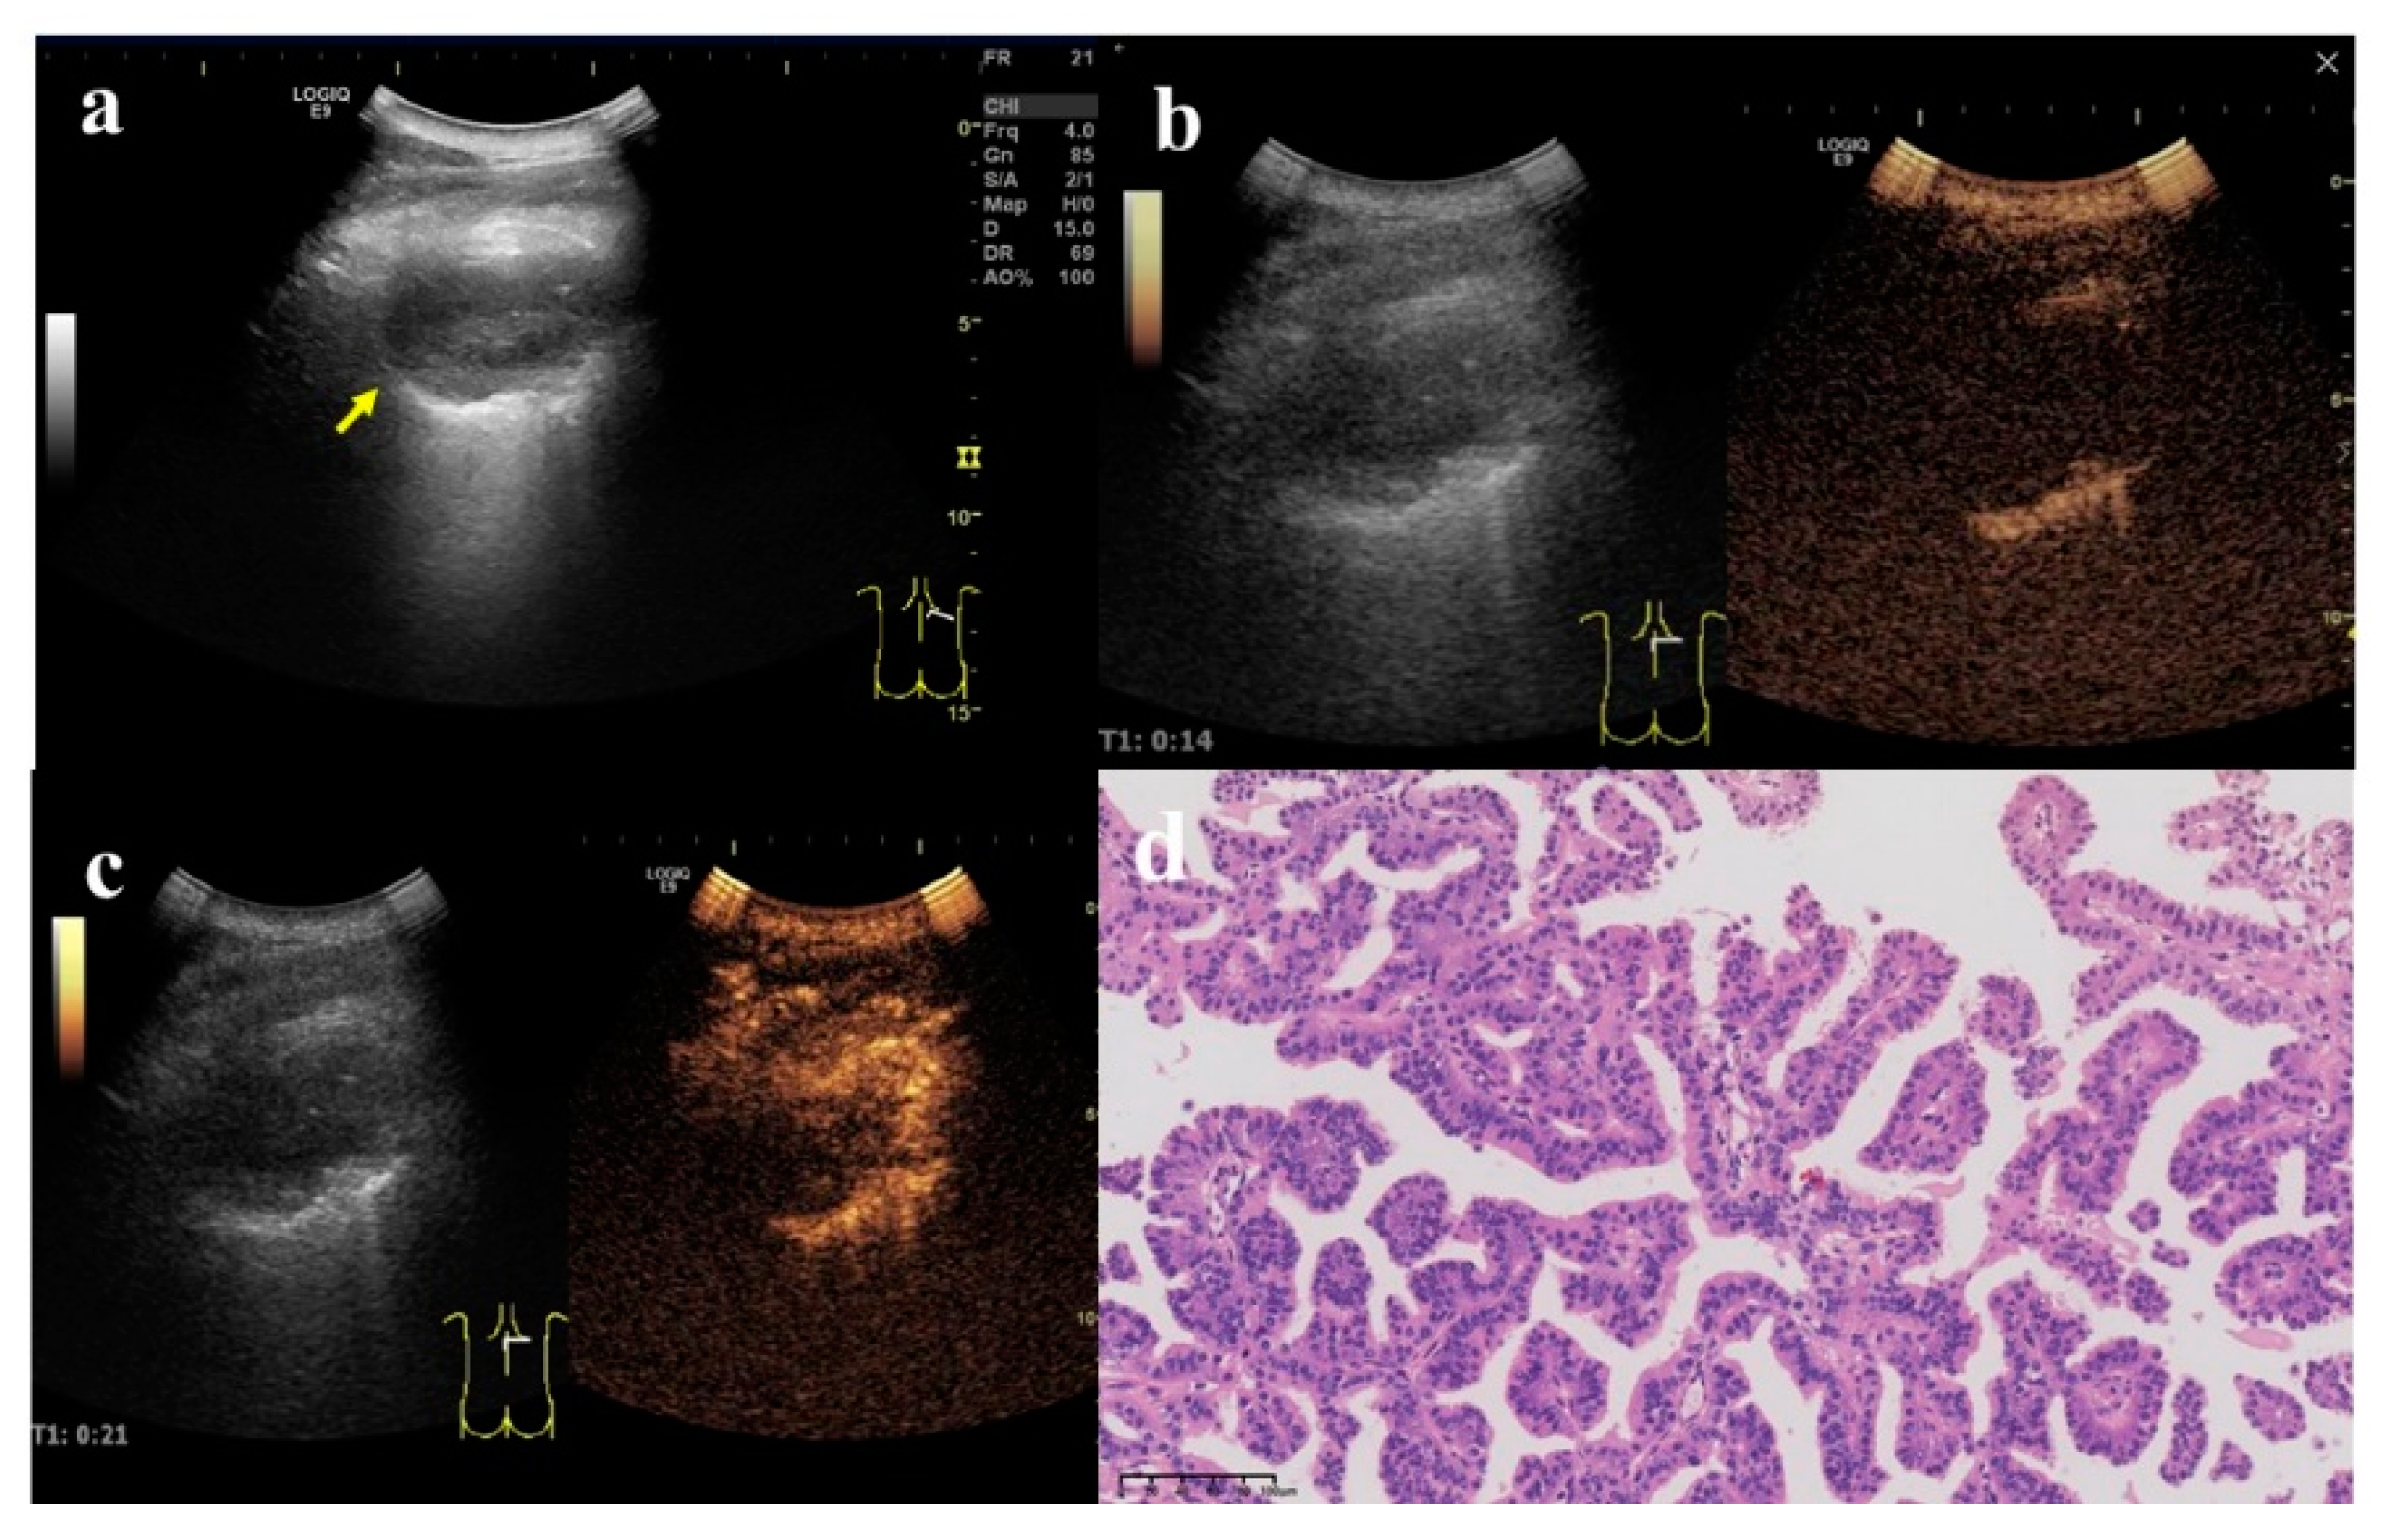

Figure 4. A 62-year-old female, who underwent total gastrectomy for gastric cancer 6 years ago and breast-conserving surgery for breast cancer 2 years ago, was coughing and expectorating for one month. (a) A wedge-shaped hypoechoic lesion (arrow) can be seen on the ultrasonic image of the right lung, with air bronchial sign inside (arrow head). Either angle between lesion border and thoracic wall was an acute angle. (b) After injection of contrast agent, the lesion began to enhance in 7 s, which was a uniform hyper-enhancement. The lung tissue began to enhance in 9 s, later than the lesion. (c) The enhancement of the lesion reached the peak in 16 s, and was a uniform enhancement. (d) An ultrasound-guided biopsy was performed. The pathological examination showed alveolar structure existed, the spacing was widened, and scattered lymphomonocytes could be seen in the focal alveolar cavity with cellulose exudation. Masson bodies (arrow) and small branch of pulmonary artery (arrow head) can be seen inside (×200). These findings conformed to the changes in organized pneumonia. After treatment with Medrol 8 mgqd for two months, the lesion became smaller and did not enlarge at the time of writing.